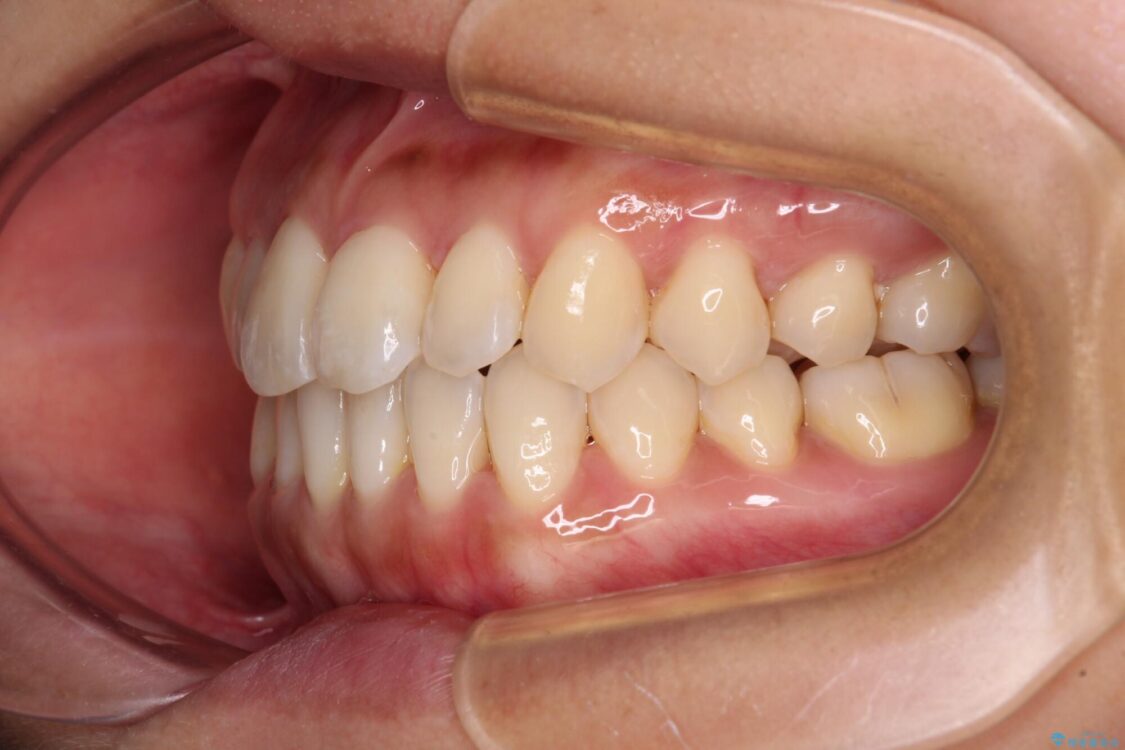

前歯のデコボコで前方に出ていることを気にして来院された患者様です。

上顎前歯が捻れて前方に飛び出しており、下顎前歯もそれに沿うようにデコボコとなっていました。

IPR(歯と歯の間を削る処置)によりスペースを獲得して上下顎前歯のデコボコを改善し、飛び出している前歯が引っ込むように設定し、インビザラインにて矯正治療を行うこととしました。

治療前